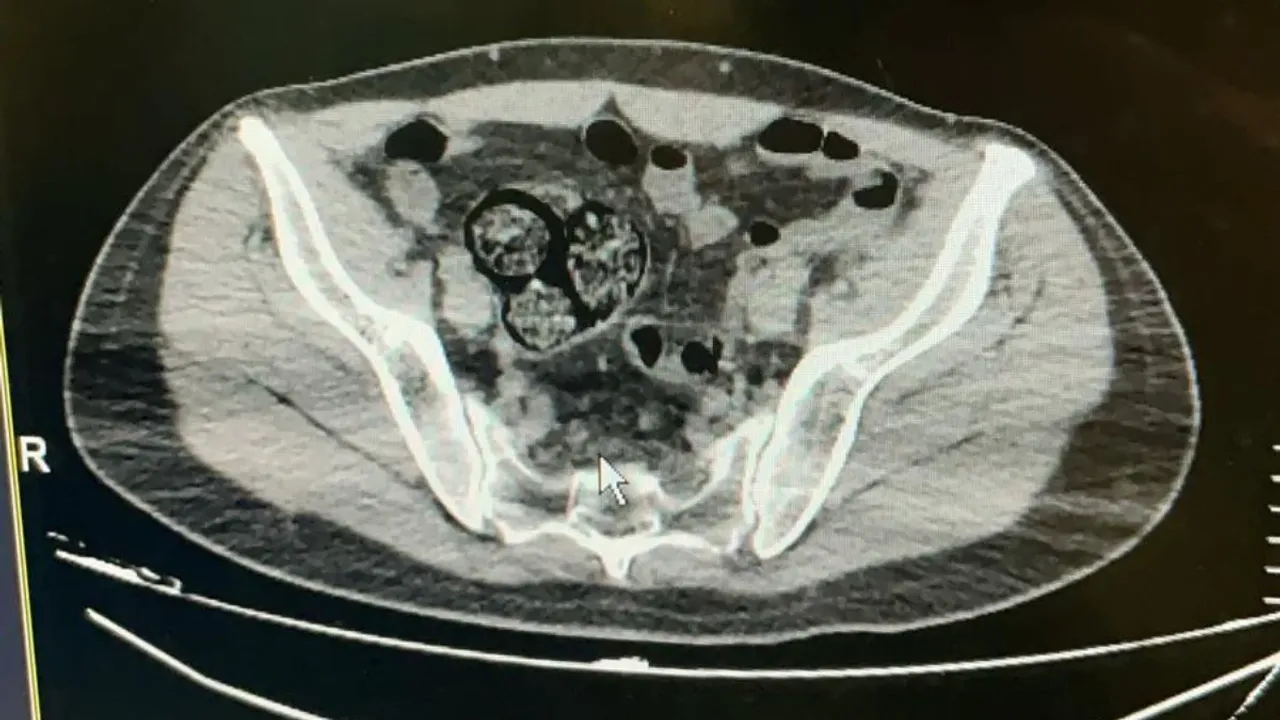

Artvin Devlet Hastanesi’ne götürülen F.R.’nin yapılan tomografisinde, bağırsaklarında 10 paket uyuşturucu madde taşıdığı belirlendi.

Şüphelinin hayati tehlike oluşturabilecek şekilde sakladığı paketler cerrahi müdahale ile çıkarıldı.